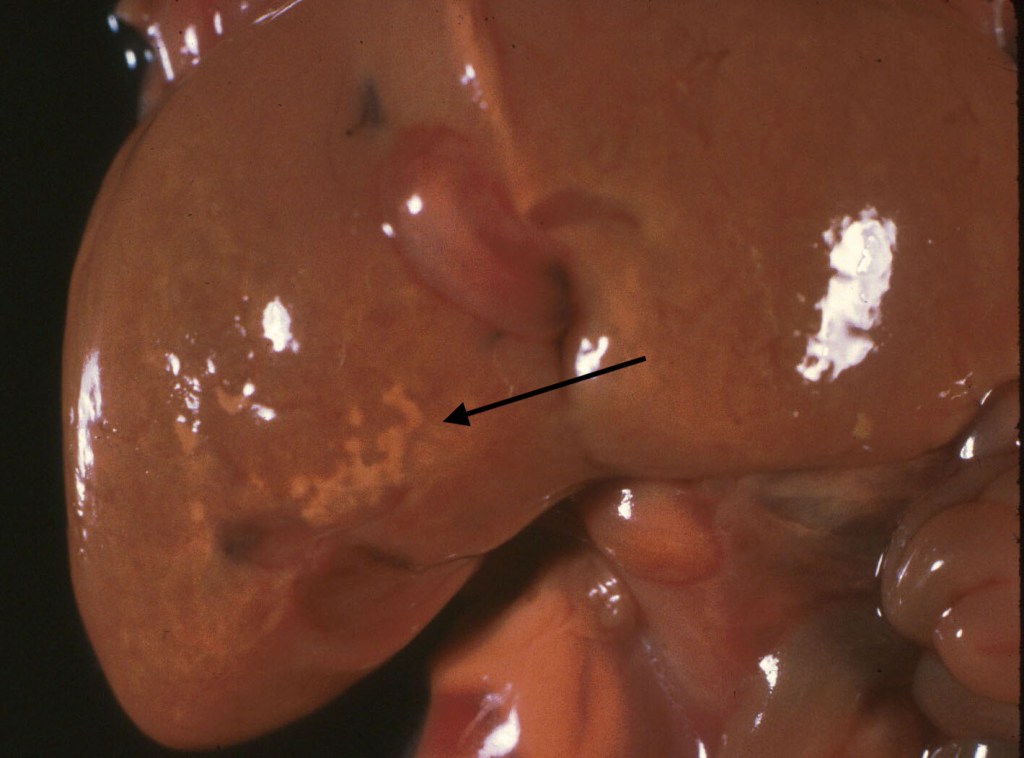

Size: The liver may be enlarged from congestion, increased erythropoiesis, and other causes (Fig 2). The liver may be smaller in growth restricted fetuses. The liver: brain ratio is a helpful judge of size, but the cause of the increase needs to be evaluated in relation to the histologic percentages of different components. The average liver brain ratio is 0.32.

Other: Some stillborn infants usually of early gestation and prolonged retention show mineralize deposits in a branching pattern on the surface of the liver, or on radiograph within the liver (Fig 3). Microscopically these lesions stain for iron and calcium and run along the portal tracks within the liver, suggestive of old periportal hemorrhage (see below).